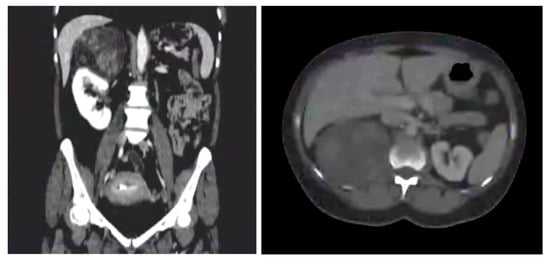

| Contrast-enhanced CT | Heterogeneous adrenal mass with fat-like attenuation displacing the right kidney and renal vein; no evidence of local invasion. | Compatible with a benign adrenal neoplasm, likely angiomyolipoma. |

| MRI | Heterogeneous mass with mixed signal intensity consistent with a fat-containing lesion. | Imaging features consistent with angiomyolipoma. |

| Diagnostic Work-Up | Contrast-enhanced CT and MRI confirmed a large adrenal lesion displacing the right kidney and renal vein. PET-CT showed increased uptake. Hormonal profile (serum catecholamines, cortisol, and urinary vanillylmandelic acid) was within normal limits. |